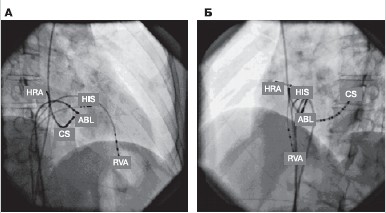

Как правило, эндоЭФИ выполняют пациентам с АВУРТ, которым планируют одномоментное выполнение РЧА при клинической аритмии. Под рентгенологическим контролем диагностические электроды устанавливают в верхнелатеральных отделах правого предсердия, в области пучка Гиса, в коронарном синусе и верхушке правого желудочка (рис. 5). Протокол эндоЭФИ у пациентов с АВУРТ включает определение антероградного эффективного рефрактерного периода АВ-соединения, точки Венкебаха, режима индукции и купирования тахикардии, методику введения синхронизированного желудочкового экстрастимула из верхушки правого желудочка, парагисиальную стимуляцию для верификации АВУРТ и дифференциальной диагностики с другими типами СВТ [8—10].

Рисунок 5. Расположение диагностических электродов внутри сердца во время проведения эндоЭФИ.

А, Б - рентгеновские стоп-кадры сердца в правой (А) и левой (Б) косых проекциях (45°) с позиционированными электродами в верхнелатеральных отделах правого предсердия (HRA), в области пучка Гиса (HIS), в коронарном синусе (CS), верхушке правого желудочка (RVA). Абляционный электрод расположен в области регистрации потенциалов медленной части АВ-соединения (ABL). эндоЭФИ - эндокардиальное электрофизиологическое исследование.